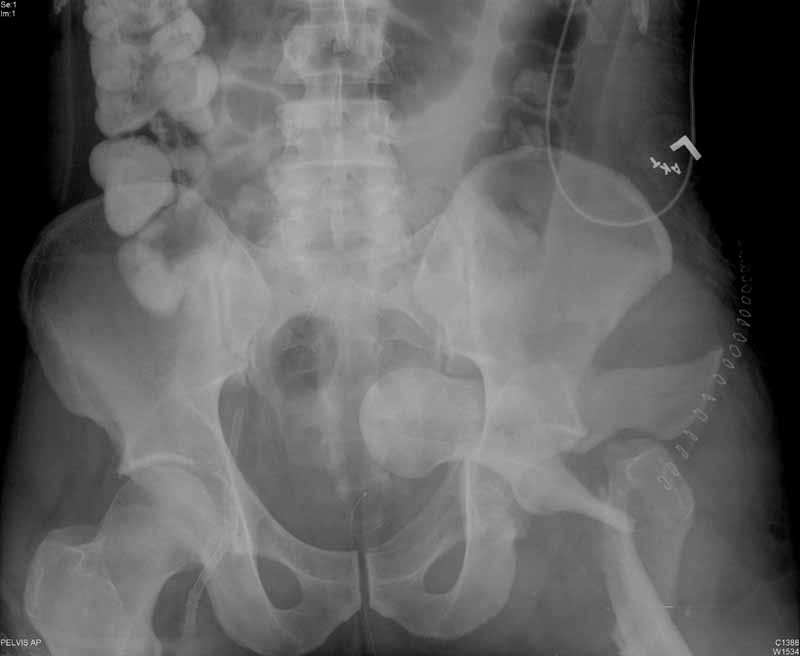

Subject: Intrapelvic fracture dislocation of the hip

Anyone ever seen one like this before? Any suggestions on how to get that thing out of there, because I tried and couldn't -got called in to the OR by a colleague with the patient already on the fracture table and 2 big incisions ( lateral and iliac crest) already made.  Gave up after an hour or two and will try again if I can figure the solution.

Yes. We used a Watson-Jones exposure, spread the acetabular fracture with a laminar spreader, and used a Schanz pin to remove the proximal femoral fragment, then fixed it, and later fixed the acetabular fracture.

I have had one very similar. I placed him lateral decubitus, did a posterior approach, and did similar to what Chip described. The posterior approach allowed me to fix what appears to be a transverse acetabular fracture. The femoral neck can be fixated from that approach with multiple screws, although there may be more there than "just" a neck fx. The patient later required hemiarthroplasty for total head osteonecrosis.